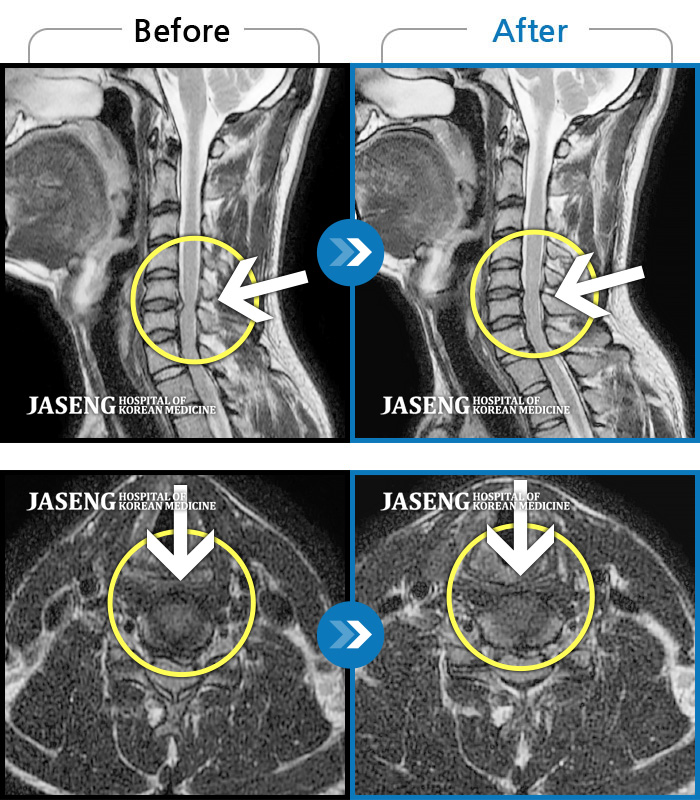

목디스크

도움받은 사례

인천 · 강아현 원장

목 통증 및 좌측 팔 저림으로 숨 쉬는 것도 불편하고 움직일 수가 없는 상태로 내원하셨습니다.

촬영시기

2023.02.13 ~ 2023.09.14

2023.09.15

조회수 110